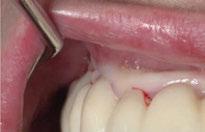

Para ilustrar el proceso, presentamos el caso de una mujer joven diagnosticada de carcinoma adenoide quístico en la región posterior del hemipaladar izquierdo (Figuras 1 y 2). El procedimiento quirúrgico realizado fue una

maxilectomía parcial que incluyó las piezas 24-26 y desde el reborde alveolar hasta la base del cráneo (Figuras 3 y 4). En este caso, la órbita y el globo ocular pudieron ser preservados. La reconstrucción inmediata se realizó mediante un colgajo de músculo temporal homolateral (Figura 5) y el defecto de la fosa temporal fue cubierto mediante una malla de titanio. Posteriormente, la paciente recibió radioterapia (Figuras 6 y 7). 2 años más tarde se diseñó un IS con anclaje en el arbotante nasomaxilar, zona subnasal izquierda

Figura 1. Imagen preoperatoria de la paciente.

Figura 2. Carcinoma adenoide quístico en región posterior del hemimaxilar izquierdo.

Figura 3. Maxilectomía parcial.

Figura 4. Defecto maxilar tras resección del tumor.